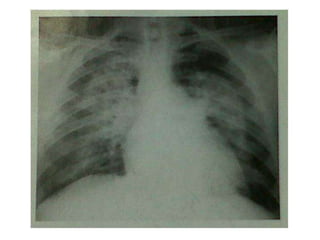

Consolidation

 Consolidation- replacement of air in one or more acini

by fluid or solid material, but does not imply a

particular pathology or etiology.

 Communications between the terminal airways allows

fluid to spread between adjacent acini- responsible for

larger area of involvement

 Commonest causes

 Acute inflammatory exudate from pneumonia.

 Non cardiogenic pulmonary oedema

 Cardiogenic pulmonary oedema

 Hemorrhage

 Aspiration

Radiologic features

 AIR BRONCHOGRAM-

 contrast between the column of air which is

present in the airway and the surrounding

opaque acini

 Normally the lung fields are radioluscent and the

bronchi are not separately visualised

 But when, there is opacification of the alveoli due

to various reasons (eg: fluid accumulation is

pulmonary oedema)the bronchi stand out as

radiolucent in contrast to the adjacent alveoli

that are radio opaque

an x-ray for a patient with right middle

zone consolidation and demonstrates

air bronchograms

Silhouette sign: If the airspace adjacent to one

of the normal mediastinal or diaphragmatic

contours is filled with dense material i.e.

consolidated, then the normal air-soft tissue

interface is lost and the normally seen edge of

the silhouette disappears

.

Upper lobe consolidation

Middle and Lower lobe consolidation

Left lower lobe consolidation